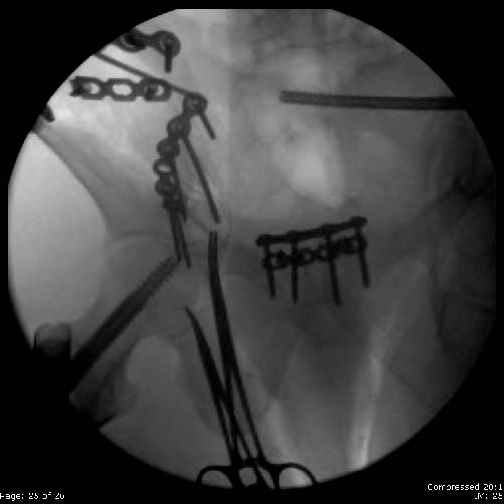

Here are the postop fluoros.

First exposed symphysis & clamped w/Faraboeuf as close to anatomic as possible.

Then extended to R ilioinguinal,really just the lateral window.

Reduced the triangular wedge piece of iliac wing to posterior intact ilium (crescent), held w/k-wire, then used 3-hole push plate to keep from moving, lagged from lat-med w 3.5 screw.

Then 6-hole plate along brim with 1 screw in R sacral ala. Then lagged 2 screws along crest A --> P. finally 10-hole plate along inner aspect of crest. R posterior ilium still a bit stepped off.

Symphysis then 'fine-tuned' & reduced as close as possible to anatomic (but, still with forward rotation of R hemipelvis - or, is it extension?) Accepted that amount of deformity and plated symph

with 4-hole symphyseal plate.

Fluoroed L SI joint and it seemed stable, but wide. So, applied c-clamp to try to squeeze down L SI joint (and note, on the last slide attached, that it's still wide), and got it closer. Single perc Iliosacral screw 40mm thread.

Applied second plate anteriorly on symphysis as I wasn't confident L SI was as stable as it could be and wanted to protect it better.

Thoughts? Thanks for the advice, it's appreciated.